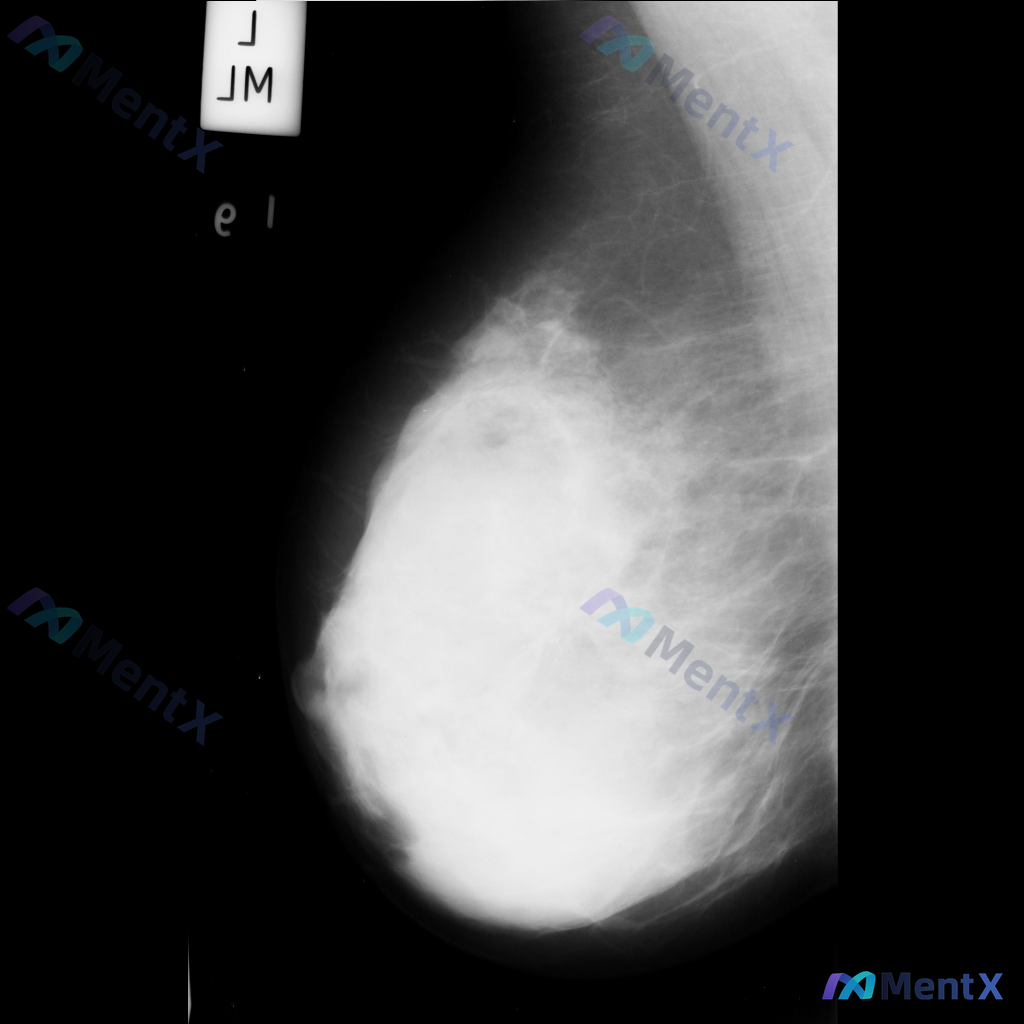

整理到一张乳腺钼靶影像的读片资料,想和大家讨论一下读片思路: 影像里能看到的主要异常是乳腺内结构扭曲(正常导管小叶结构有集中、牵拉、不规则向中心汇聚的表现,但没有明确肿块),同时还有不对称致密影(局部组织密度增高,和周围或对侧分布不太一致)。另外,乳腺本身纤维腺体组织偏多,可能属于 BI-RADS...